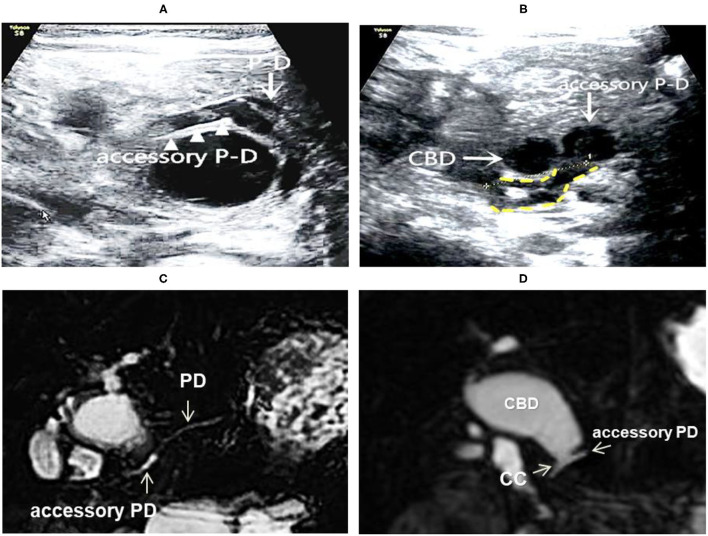

On the basis of the new JSPBM’s classification, the individual morphologic features of PBM were described as four types (ref. 11) in presenting our ultrasound report: type A (stenotic)—the distal CBD with stenosis before joining with the CC, and an angle of slightly < 90° usually observed in the conjunction between PD and CBD at a site distant from the papilla of Vater; type B (non-stenotic)—the distal CBD emerging but without stenosis pattern before joining with the CC, in addition, an approximately right angle customarily seen in the conjunction between PD and CBD at a site distant from the papilla; type C (dilated channel)—the dilated CC significantly occurred; type D (complex)—a complicated configuration in PBJ contexture including the PD, the terminal portion of the CBD, and the dilated accessory PD, and one end opening as a small nipple in the duodenum and the other end converged with the CBD downward into the CC. Figures 1–4 show the representative imagines of A, B, C, and D types of PBM, respectively.

Among the 31 cases, 14 cases were stenotic type (A), 11 cased were non-stenotic (B), and five were dilated channel (C). The complex type (D) rarely occurred and only one case was found in our medical center. Table 3 shows the comparison among A, B, and C types in terms of gender, age, the maximum internal diameter of CBD, the internal diameter of CC, the length of CC, the internal diameter of the main PD, and the thickness of the gallbladder. Type A causes a significant increase in the internal diameter of CBD. Type C appears significant increases in internal diameter and length of CC and internal diameter of PD.